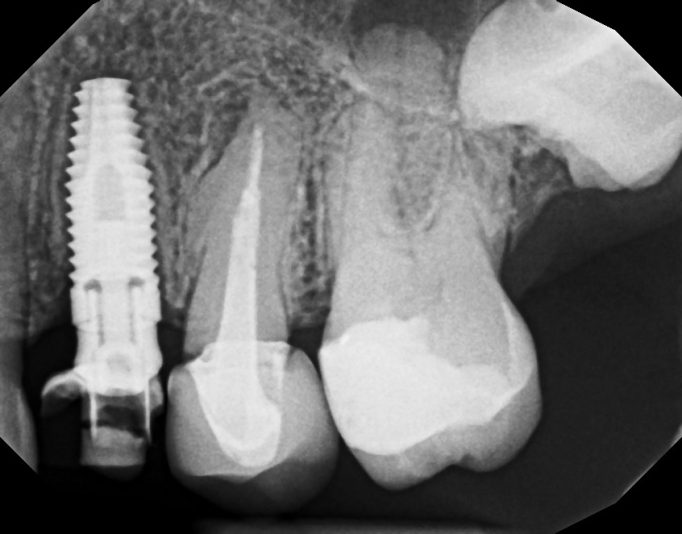

I placed this implant 8 months ago. It was immediate placement. I did the uncovery today. The pre op radiograph shows some loose bone graft. I didn’t really notice anything off upon flapping . ISQ 77. Is it something I should be concerned about?

So I suspect the implant was placed in cortical bone at the top and the lack of blood supply caused this die off. It could also be the lack of KT thickness. This is why I routinely place my implant 2mm subcrestal. At this point I don’t think there’s anything that can be done. It’ll be ok, just something to remember for next time.

It doesn’t look like it will be a problem. Some of the graft turns over into natural bone–but some (like the graft stuck in soft tissue shown above your implant) will not turn over. It’s ok.